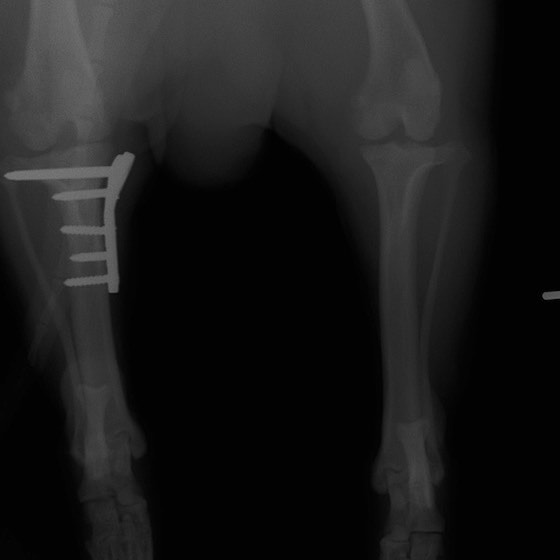

雑種 5歳

左後肢の挙上を主訴に来院されました。触診にて両関節の前方引き出し兆候、両膝蓋骨の内方脱臼を認めました。関節液検査より免疫介在性多発性関節炎は否定的でした。レントゲン検査にてfat pad signを伴う関節炎が認められたことから、前十字靭帯断裂と膝蓋骨内方脱臼(左GradeⅢ 右GradeⅢ〜IV)併発と診断し、手術を行いました。

手術は片足ずつ行い、両膝とも術中の関節鏡検査にて前十字靭帯の完全断裂と半月板損傷を確認しました。TPLO、半月板切除と滑車溝形成を始めとした膝蓋骨脱臼整復術を実施いたしました。膝蓋骨の安定化を測るために外側支帯を強固に縫合し、内側支帯は切除し縫合せずに開放状態にしています。

術後の歩行状態は良好です。

術前のTPAは左後肢33.1°右後肢26.8°でしたがTPLO実施により左後肢5.5°右後肢12°に矯正されました。